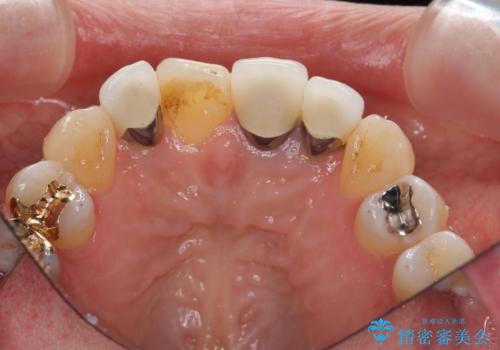

- 前歯のクラウンの歯肉の位置が年々変化し、歯ぐきのフチが黒くなってしまった、綺麗にしたいと希望されて来院されました。

装着されているセラミッククラウンを除去したのち、現在の歯ぐきのラインにしっかりと合う精度の高いオールセラミッククラウンを作製していきます。